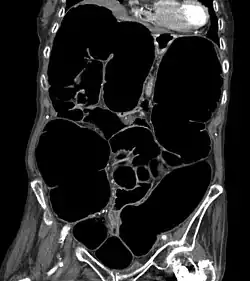

CT-Scan showing a coronal section of the abdomen of an elderly lady with an IPO.

The symptoms of IPO are nonspecific. It is not unusual for patients to present repeatedly and to undergo numerous tests.[4] Mechanical causes of intestinal obstruction must be excluded to reach a diagnosis of pseudo-obstruction. Attempts must also be made to determine whether the IPO is the result of a primary or secondary condition.[15] A diagnostic work-up may include:[14]

• CT-Scan showing a Cross-section of the abdomen of an elderly lady with an IPO.